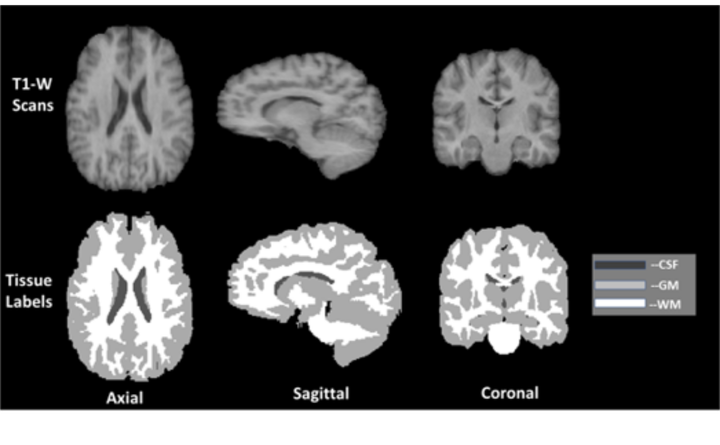

Graphical description of IBSR 01 volume and corresponding ground truth labels.

Automatic segmentation of brain Magnetic Resonance Imaging (MRI) images is one of the vital steps for quantitative analysis of brain for further inspection. In this paper, NeuroNet has been adopted to segment the brain tissues (white matter (WM), grey matter (GM) and cerebrospinal fluid (CSF)) which uses Residual Network (ResNet) in encoder and Fully Convolution Network (FCN) in the decoder. To achieve the best performance, various hyper-parameters have been tuned, while, network parameters (kernel and bias) were initialized using the NeuroNet pre-trained model. Different pre-processing pipelines have also been introduced to get a robust trained model. The model has been trained and tested on IBSR18 data-set. To validate the research outcome, performance was measured quantitatively using Dice Similarity Coefficient (DSC) and is reported on average as 0.84 for CSF, 0.94 for GM, and 0.94 for WM. The outcome of the research indicates that for the IBSR18 data-set, pre-processing and proper tuning of hyper-parameters for NeuroNet model have improvement in DSC for the brain tissue segmentation.